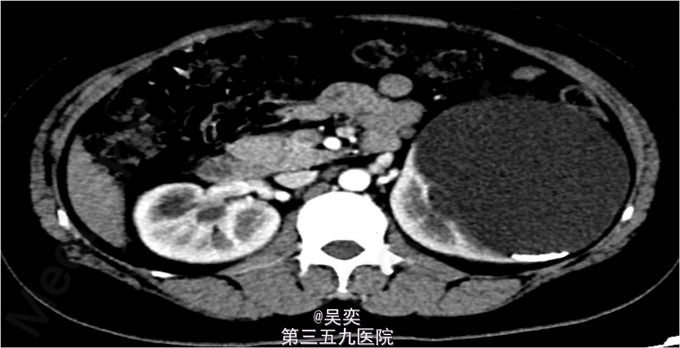

3、查体:无阳性体征 4、辅助检查:我院泌尿系B超:右输尿管上段结石并上段扩张,双肾多发结石。入院后白细胞总数10.550x10E9/L,中性粒细胞绝对值6.970x10E9/L。尿常规:白细胞计数50.30个/ul,红细胞计数145.70个/ul。生化全套:谷丙转氨酶75.000U/L,谷草转氨酶44.000U/L。双肾CTU:1、左肾盂和中下盏铸型结石较前稍增多,左肾中度积水。2、右肾多发结石,右肾中度积水,右侧输尿管上段炎症。3、左肾上极巨大囊性病变较前增大,考虑扩张的肾盏,内有结石。4、盆腔多发静脉石。5、前列腺小钙化灶。其余术前常规抽血结果无特殊。

5、诊断:肾积水伴输尿管结石,肾结石,精神分裂症 6、入院后完善相关检查,心电图、胸片未见异常,CT示:1、左肾盂和中下盏铸型结石较前稍增多,左肾中度积水。2、右肾多发结石,右肾中度积水,右侧输尿管上段炎症。3、左肾上极巨大囊性病变较前增大,考虑扩张的肾盏,内有结石,排除手术禁忌症,经术前准备,于左侧经皮肾镜碎石取石术,手术顺利,术后恢复较好。